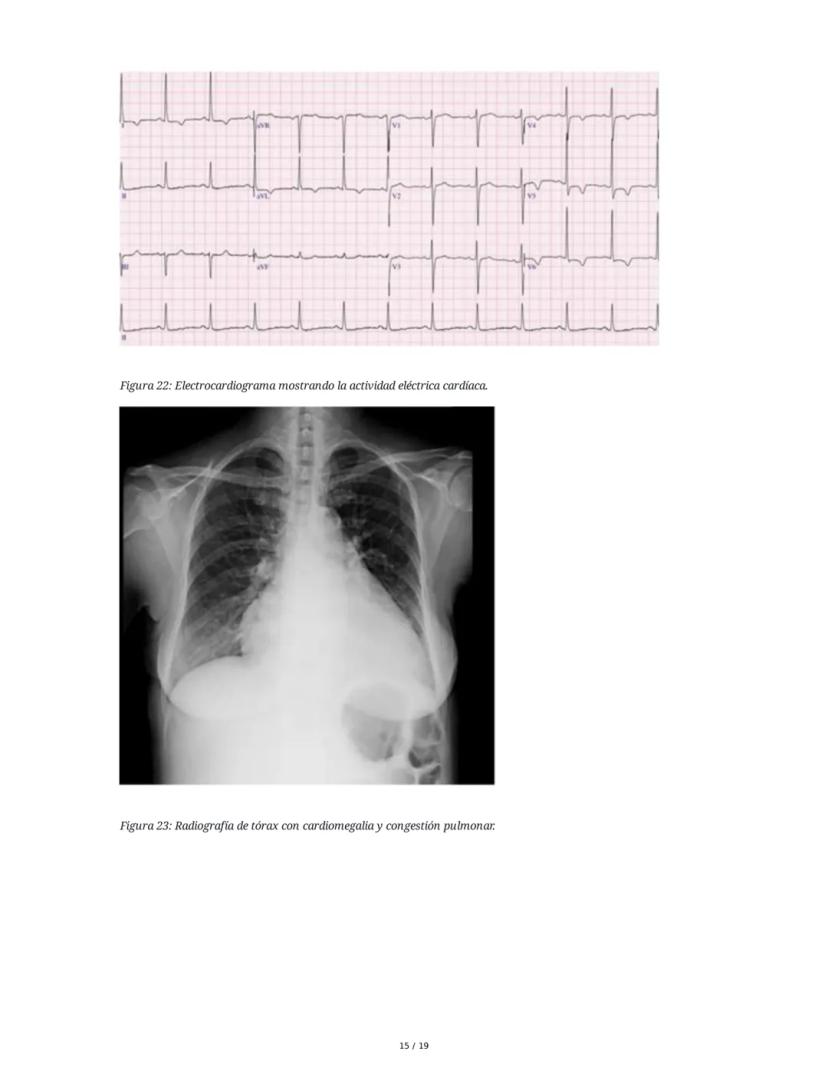

Las pruebas complementarias fundamentales incluyen: